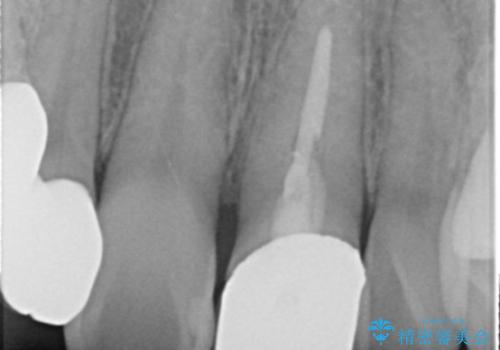

- 前歯の被せ物のやり替えを希望して来院されました。

再根管治療の後、審美性の良いジルコニアクラウンをセットしていきます。